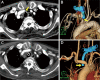

Fig. 2

Endovascular procedure. A 12 Fr long sheath and guide wire were inserted from the right brachial artery, and a pigtail catheter was inserted from the right common femoral artery. Diagnostic imaging showed the entrance of the right brachiocephalic innominate artery and no obvious bleeding source (A). A covered stent made of polytetrafluoroethylene (VIABAHN; 13 mm × 50 mm) was placed so that it did not reach the origin of the common carotid artery and so that it covered the fistula definitively (arrow: distal end of covered stent; arrowhead: proximal end of covered stent) (B, C, D).